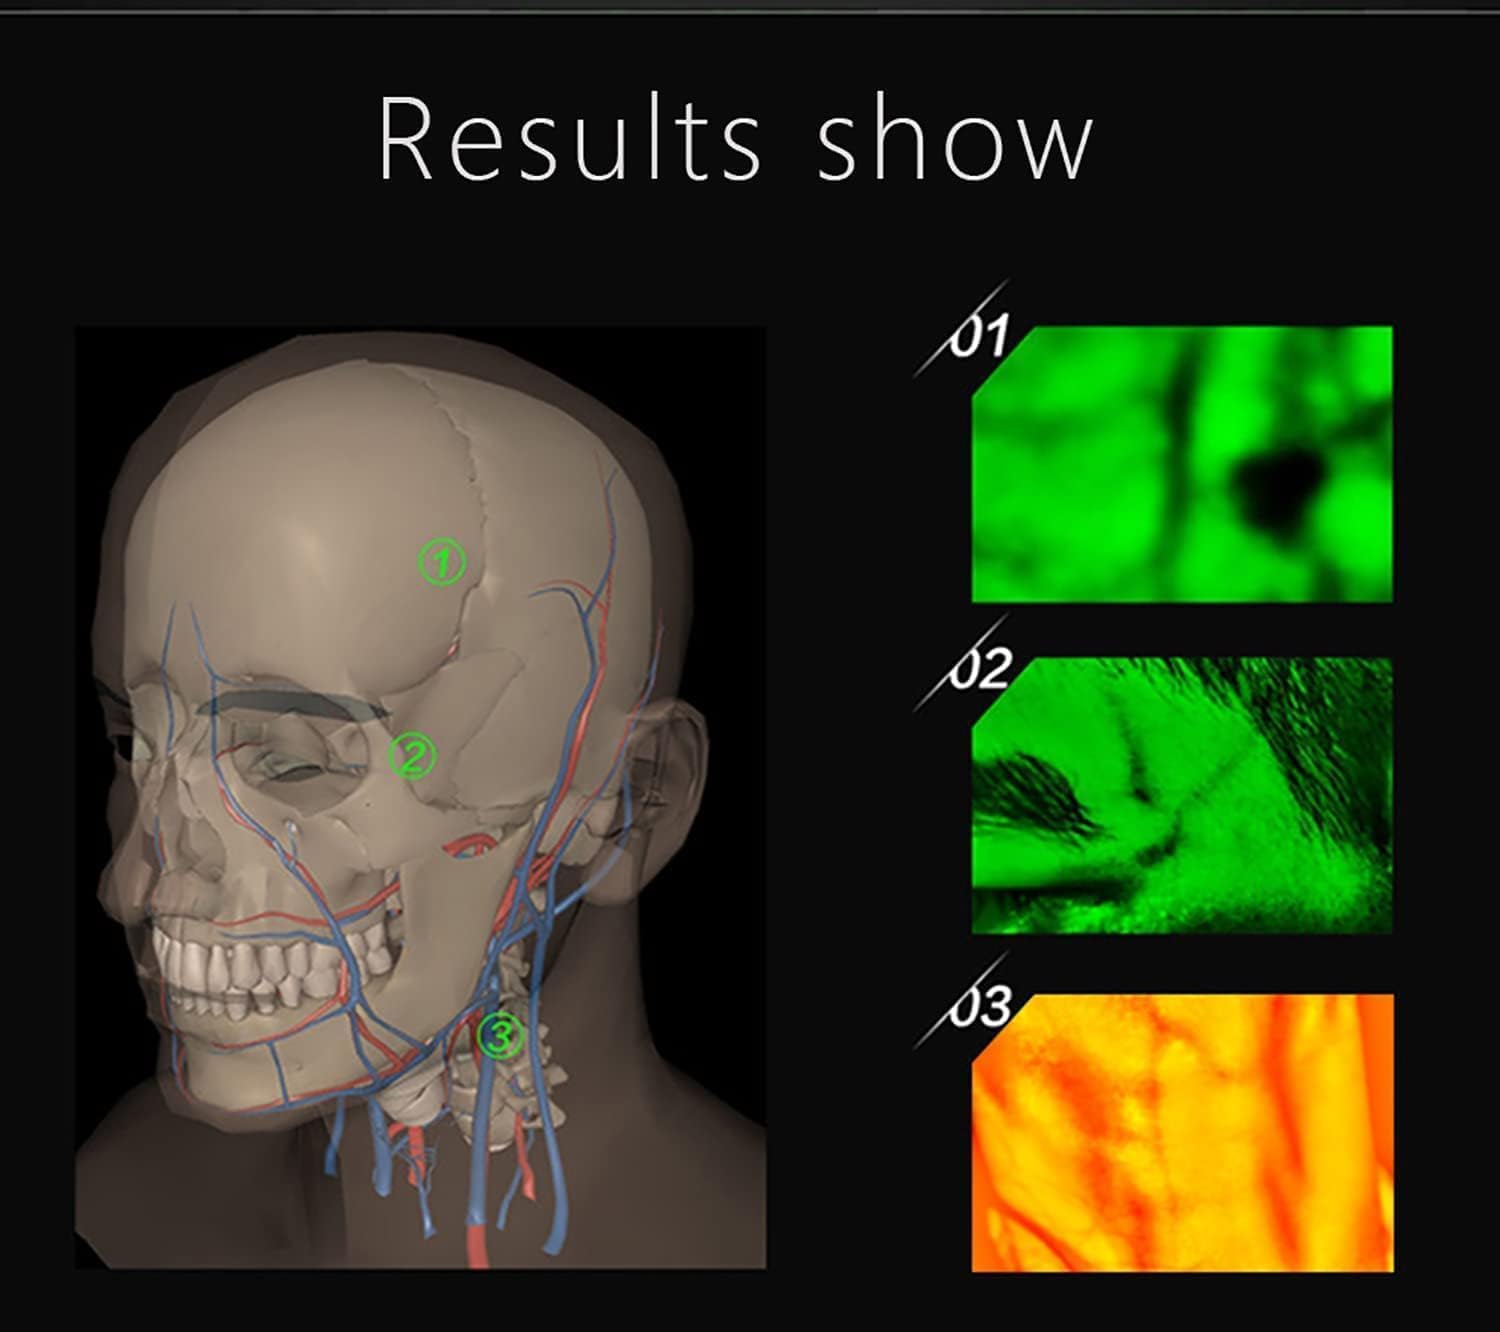

Our medical vein finder device adopts the principles of hemoglobin strong absorption of infrared light,

designed the helpful vein finder device, which consists of infrared vein collector & vein recognition system